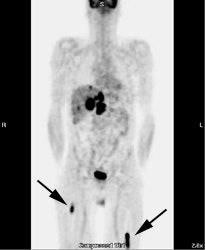

Osseous lymphoma: Unsuspected focal osseous involvement of the femurs was identified on PET imaging of this patient with newly diagnosed B-cell non-Hodgkin's lymphoma (black arrows). Extensive hepatic involvement was seen within the abdomen, but there were no other sites of bone disease. Focal bone disease such as this will not be detected on bone marrow biopsy. |

|

In one study, PET imaging revealed osseous involvement not detected on bone marrow biopsy in 12.8% of patients [6]. This finding resulted in an increase in patient stage in 10% of patients [6]. In that same study, bone marrow biopsy revealed tumor involvement in 5% of patients that was not detected by FDG-PET imaging [6]. However, the cases in which FDG-PET was false negative involved low- or intermediate-grade lymphomas with only discrete displacement (up to 10%) of normal marrow [6]. Because the degree of FDG uptake declines in a lower grade of malignancy -- the combination of lower numbers of malignant cells and low FDG tumor uptake likely resulted in low marrow activity [6].